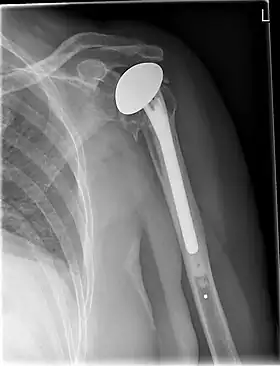

![]() X-ray of a shoulder prosthesis | |

Shoulder replacement is a surgical procedure in which all or part of the glenohumeral joint is replaced by a prosthetic implant. Such joint replacement surgery generally is conducted to relieve arthritis pain or fix severe physical joint damage.[1]

Various materials can be used to make prostheses, however the majority consist of a metal ball that rotates within a polyethylene (plastic) socket. The metal ball takes the place of the patient's humeral head and is anchored via a stem, which is inserted down the shaft of the humerus. The plastic socket is placed over the patient's glenoid and is typically secured to the surrounding bone via cement.[12]